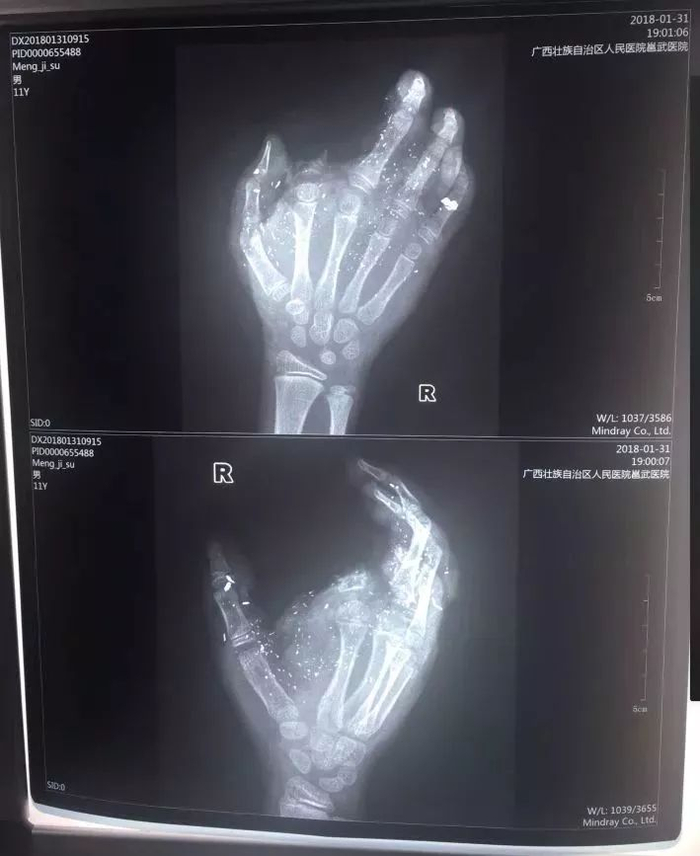

急诊科兰天兵医生介绍,孩子送来时伤势很重。右手食指被炸没了,拇指、中指、无名指也都炸伤,失去了供血,手掌皮肤被炸得稀烂。经CT检查,右眼内有2块手机碎片。

记者从医院了解到,孩子断的那根手指已经植不回去了。目前手术通过血管移植,让孩子损伤的另外3个手指恢复了血供,预计今后不会对功能造成太大影响。